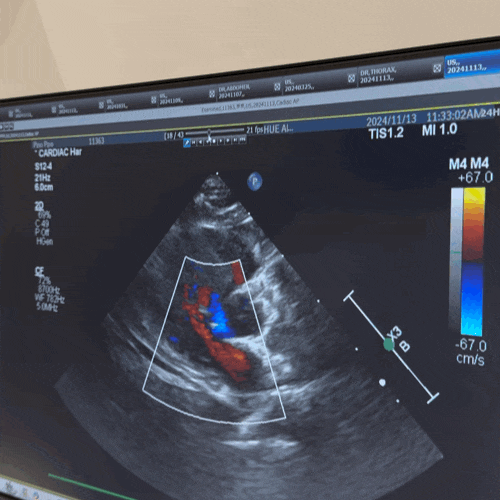

부산 강아지 심장병 동물병원 24시 더휴동물의료센터 고양이 심근비대증 지방종 검사

[온천장] 부산 고양이 동물병원 24시 더휴 동물의료센터 심장초음파 연중무휴 ❗️주차 O ❗️입원 O ❗...